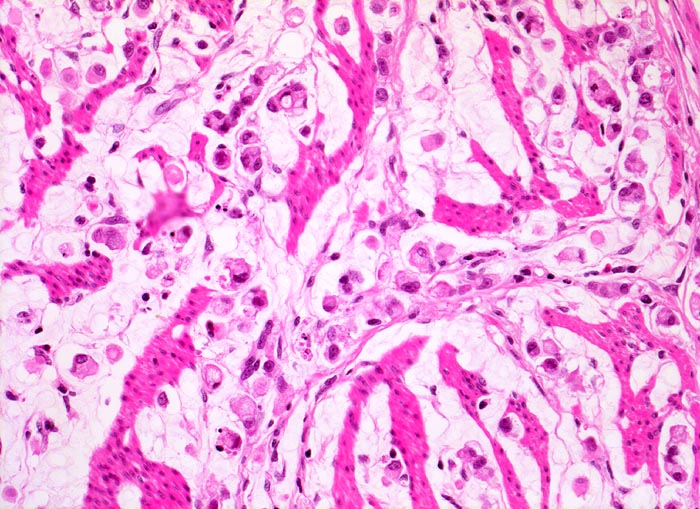

PathoPic – image database / PathoPic ID 3386 - Adenokarzinom des Magens mit Siegelringzellen

Adenokarzinom des Magens mit Siegelringzellen

Ein Grossteil des Tumorinfiltrats besteht aus einzeln liegenden Siegelringzellen mit intrazytoplasmatischen Schleimvakuolen. Zwischen den Tumorzellen liegen Reste der Magenwandmuskulatur.

Diffuse Verdickung und Versteifung der Magenwand im Sinne einer Linitis plastica bei intakter Schleimhautoberfläche. Aufhebung des Faltenreliefs.